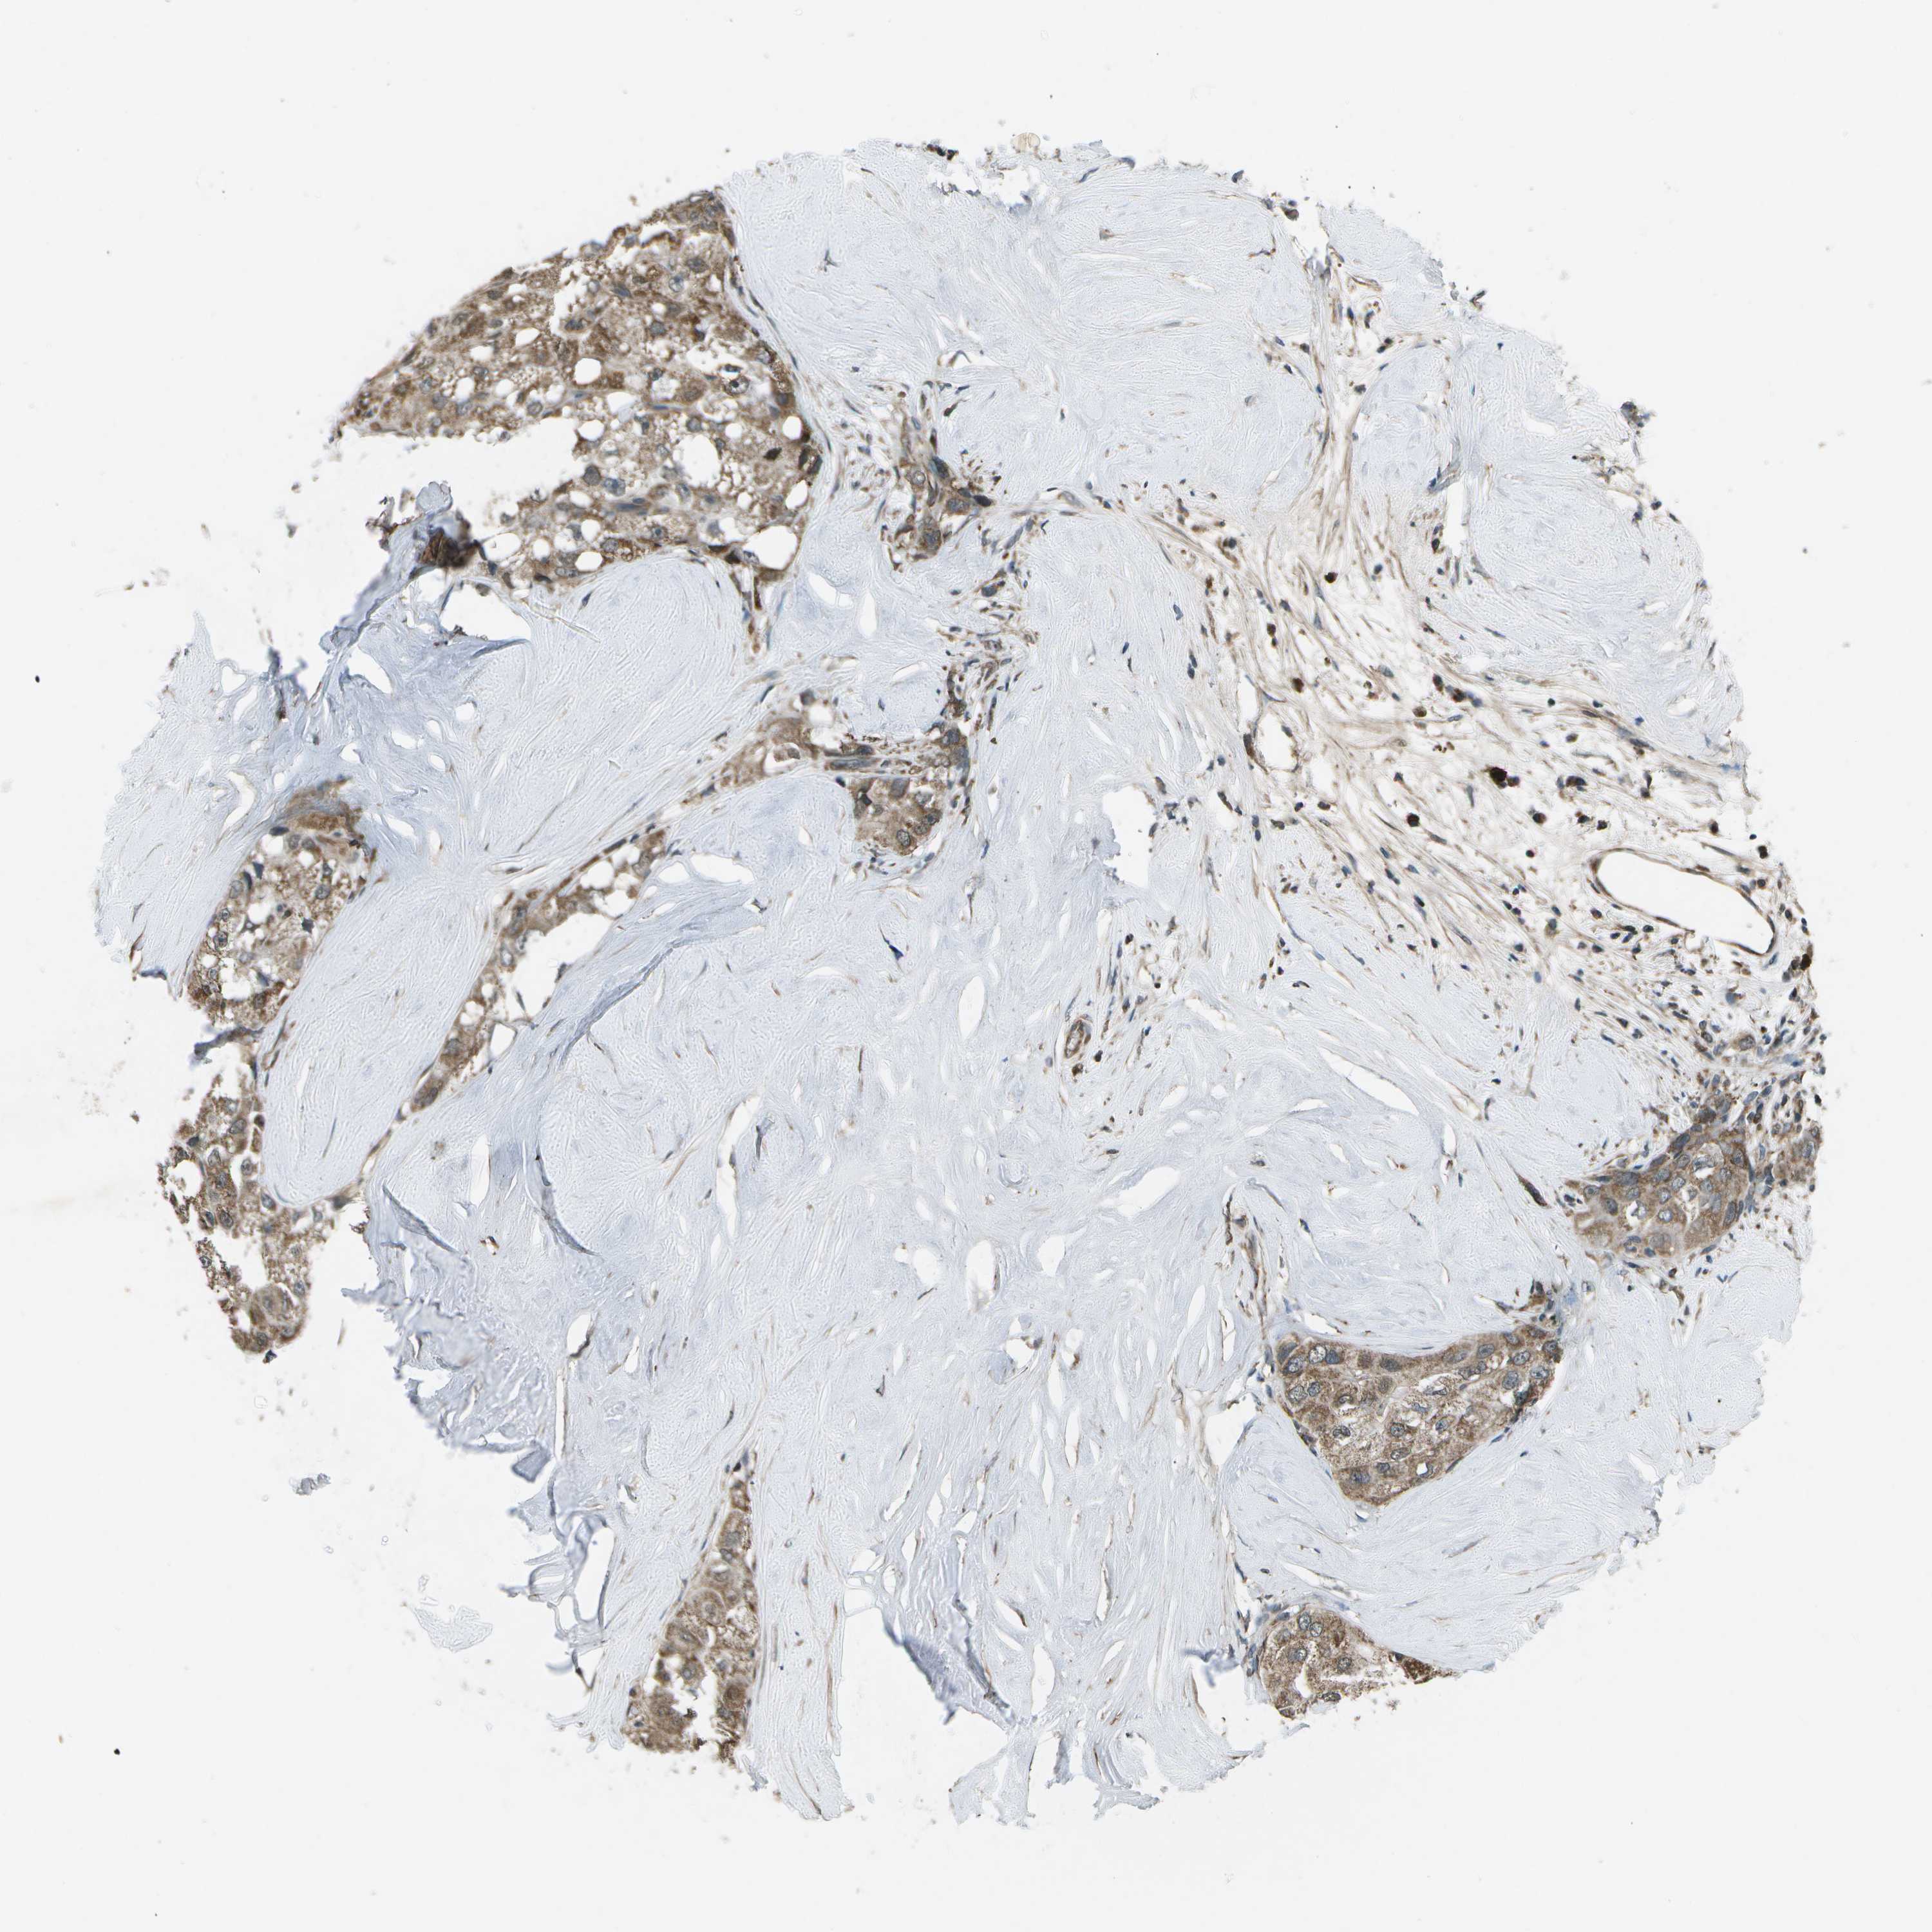

LIVER CANCER - Protein expressioni

A mouse-over function shows sample information and annotation data. Click on an image to view it in a full screen mode. Samples can be filtered based on level of antibody staining by selecting one or several of the following categories: high, medium, low and not detected. The assay and annotation is described here.

Note that samples used for immunohistochemistry by the Human Protein Atlas do not correspond to samples in the TCGA dataset.

Antibody stainingi

Antibody staining in the annotated cell types in the current human tissue is reported as not detected, low, medium, or high, based on conventional immunohistochemistry profiling in selected tissues. This score is based on the combination of the staining intensity and fraction of stained cells.

Each image is clickable and will lead to virtual microscopy that enables deeper exploration of all samples and also displays staining intensity scores, fraction scores and subcellular localization as well as patient and tissue information for each sample.

Antibody HPA016496

Antibody CAB022082

Staining

High

Medium

Low

Not detected

Intensity

Strong

Moderate

Weak

Negative

Quantity

>75%

75%-25%

<25%

None

Location

Nuclear

Cytoplasmic/membranous

Cytoplasmic/membranous,nuclear

Cholangiocarcinoma

Carcinoma, Hepatocellular, NOS